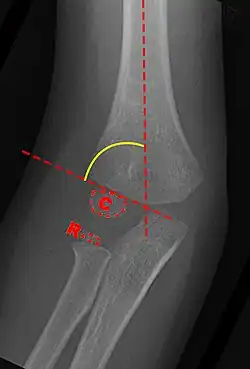

Carrying angle can be evaluated through AP view of the elbow by looking at the Baumann's angle.[3] There are two definitions of Bowmann's angle:

The first definition of Baumann's angle is an angle between a line parallel to the longitudinal axis of the humeral shaft and a line drawn along the lateral epicondyle.

Another definition of Baumann's angle is also known as the humeral-capitellar angle. It is the angle between the line perpendicular to the long axis of the humerus and the growth plate of the lateral condyle. Reported normal values for Baumann's angle range between 9 and 26°.[7] An angle of more than 10° is regarded as acceptable.[7]